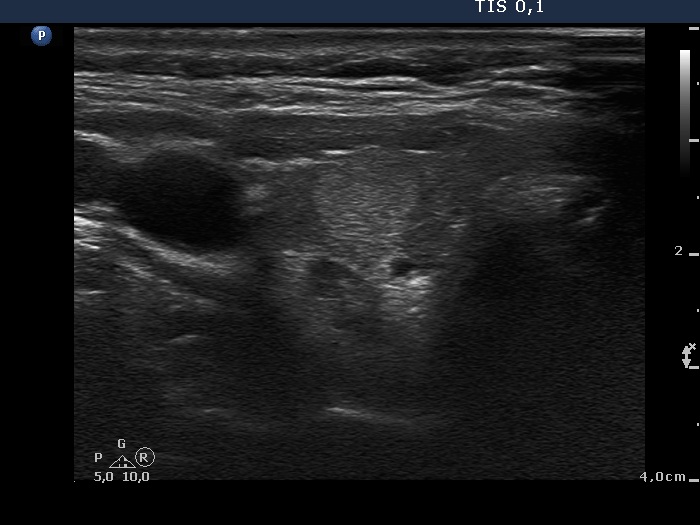

Ultrasonography. The thyroid was minimally-moderately hypoechogenic. There was a hyperechogenic nodule in the central part of the right lobe while several small insignificant lesions in the left thyroid. There was a hypoechogenic mass in the border of the middle-lower part of the right lobe dorsolateral. The lesion presented no vascularity.